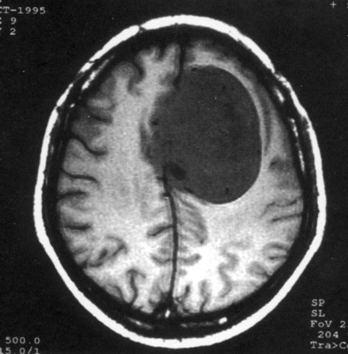

问题 病历摘要:??患者女性,37岁。大便时突起炸裂样头痛3小时,伴喷射样呕吐。既往体健。体检:T37.5℃,BP145/90mmHg,R20次/分,P85次/分。神志清楚,颅神经检查无异常,颈强直,克、布氏征(-),四肢肌力、肌张力正常,病理征(-)。 动脉瘤术中出血时,可采取哪些措施?提示:入院后第?2日患者行右翼点开颅瘤颈夹闭术,术中分离瘤颈时,动脉瘤破裂。